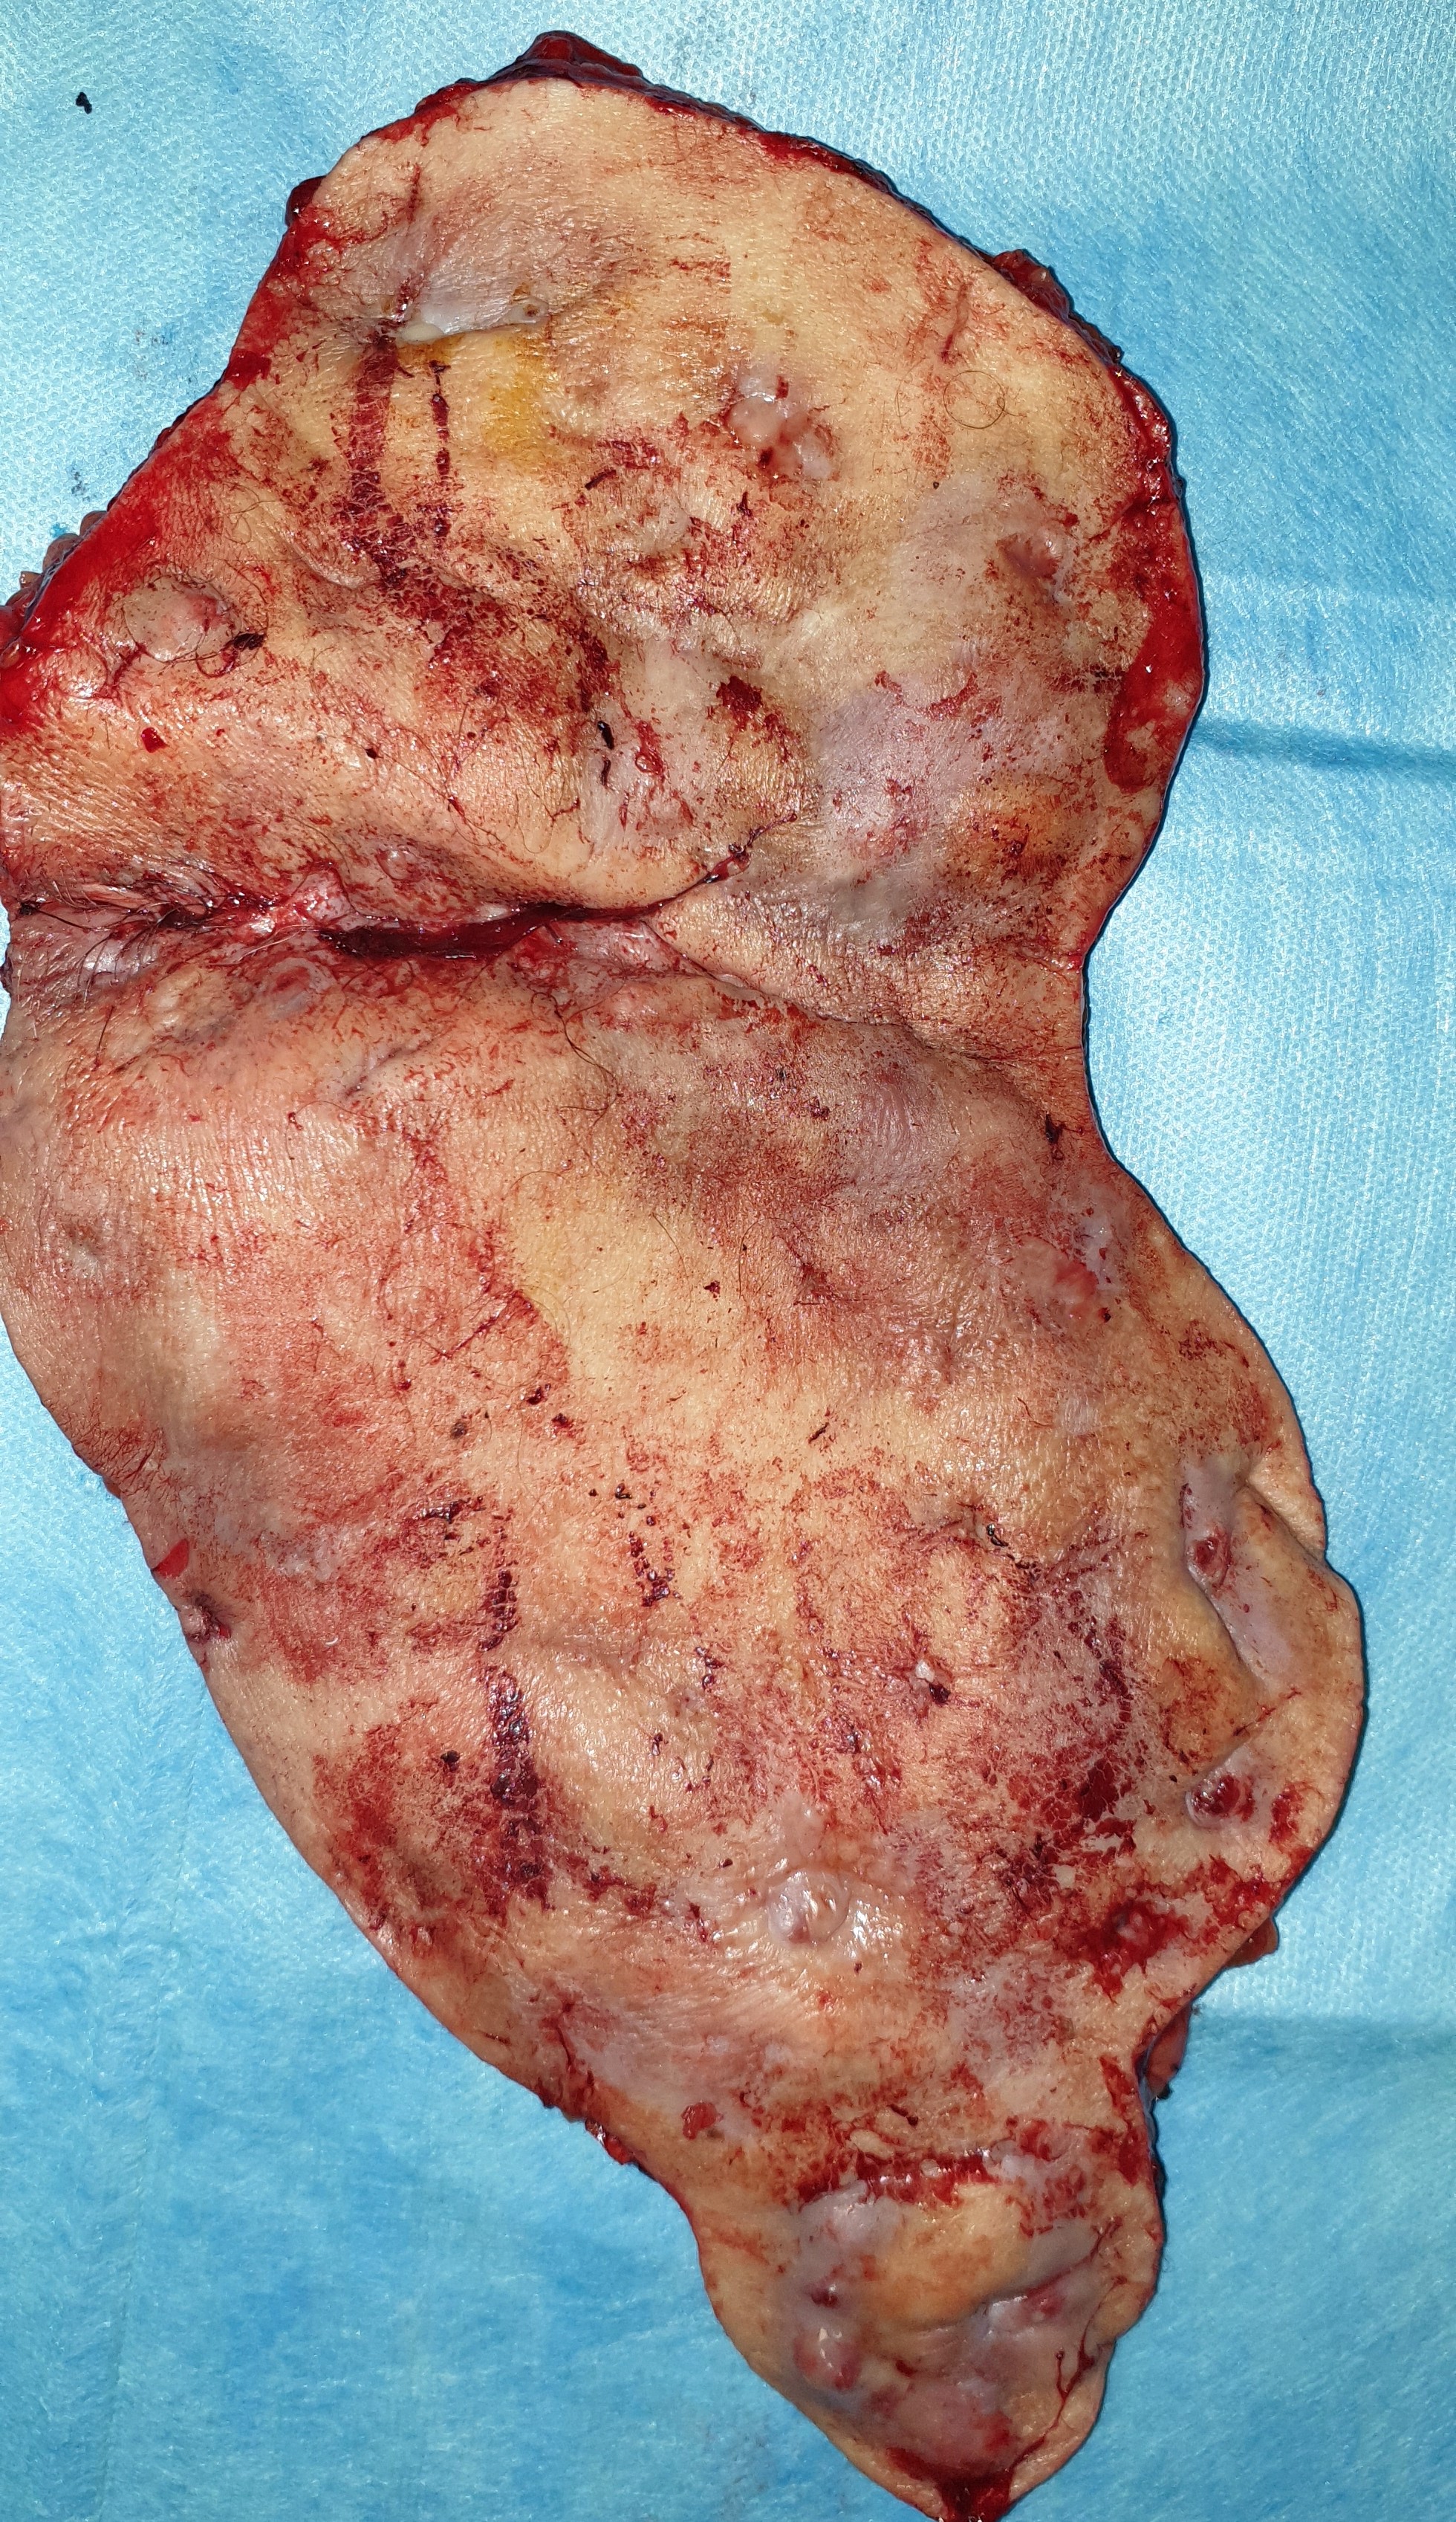

Σχήμα 2 . Εξαγόμενος όγκος - Επιφάνεια κοπής (ευγενική παραχώρηση Δρ. Β. Πενόπουλος) .